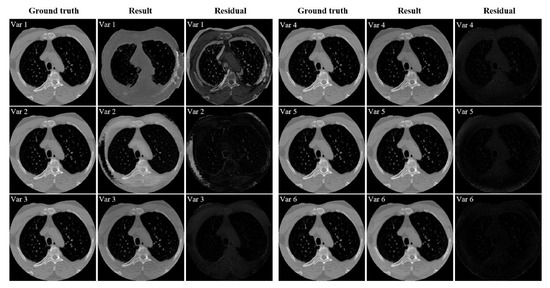

- Var1: only the adversarial loss is introduced in the network.

- Var2: the reconstruction loss is added to Var1.

- Var3: the artifact consistency loss is introduced to Var2.

- Var4: the cycle consistency loss is added on the basis of Var3.

- Var5: the polar coordinate transformation is incorporated into Var4.

- Var6: the total variation loss is added to Var5, and this is the final network configuration.

| Var1 ( only) | 0.7838 | 24.5578 |

| Var2 (Var1 with ) | 0.9232 | 31.2989 |

| Var3 (Var2 with ) | 0.9573 | 33.7104 |

| Var4 (Var3 with ) | 0.9710 | 35.8856 |

| Var5 (Var4 with polar transformation) | 0.9805 | 37.5096 |

| Var6 (Var5 with ) | 0.9873 | 39.7273 |